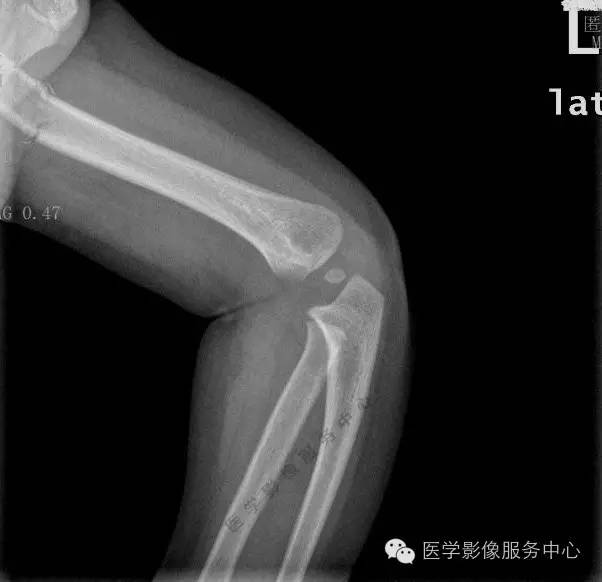

影像图片

你能发现问题吗?

相信大家都看到了吧,肘关节没问题,肱骨骨折。急诊基本都是小医生在做,现在工作量又大,平片最忌一下就盯住阳性的或临床医生申请的,但是现在的临床医生有几个认真望触叩听的,千万别太相信他们!出了事尽量往辅助科室推是他们临床的潜规则,所以急诊一定要认真,片子上的全都要看一下,我习惯先看不重要的然后才看重要的,真的遇到好几次这种情况,拍肋骨正斜位结果锁骨或肩胛骨骨折的都不知道多少个了,我科技术员习惯站着拍,可倒好!连拍肩关节气胸的或肺挫伤的都有!还有一次拍骨盆结果腰椎骨折,拍腰椎结果带到的一根肋骨骨折,最夸张的一次我科纠纷,外伤颈椎正侧位,结果有次第1肋骨骨折漏掉了!没办法临床弱辅助科室想不漏诊都难!

本例我科漏诊原因我认为

1是被误导,但是小儿外伤定位较难,技术员拍片连光圈、球管都懒得调的,致使明明拍一个部位结果会显示很多其他的;

2是只有侧位看见骨折线,但是骨折线又紧邻家长扶着的手边,很容易以为是外边的伪影,说实在的要不是那个小骨片刚开始我也以为是伪影呢。